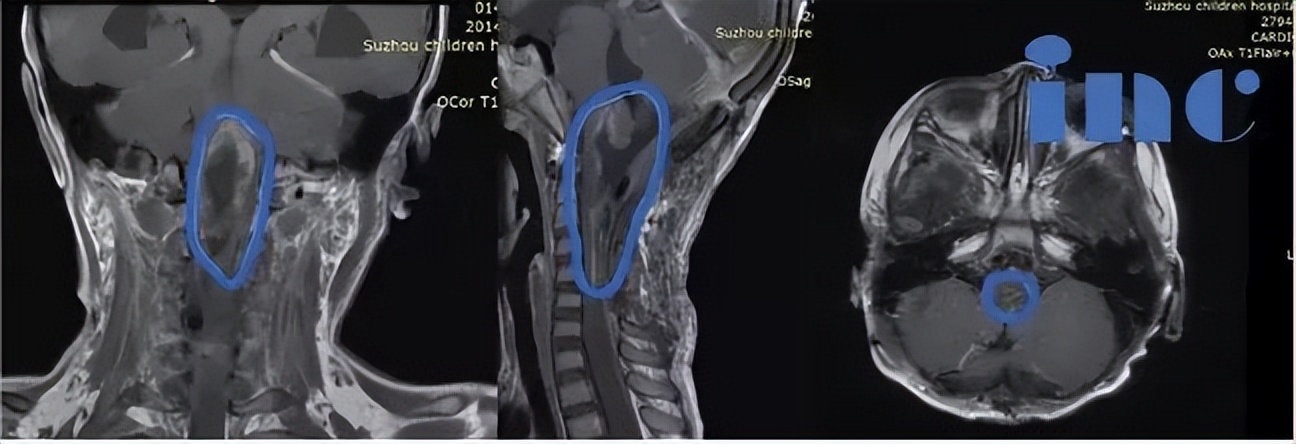

6岁女孩脑干延髓巨大胶质瘤获95%以上切除

患者情况:6岁女孩,脑干胶质瘤,肿瘤位于脑干延髓一直延伸至颈5节段脊髓,国内医生均表示风险太大,无手术机会。

治疗过程:2019年在INC德国巴特朗菲教授国内手术示范期间接受这位德国专家主刀手术,肿瘤切除率高达95%以上。

术后情况:术后ICU留观1天,神志清楚,完全自主呼吸,拔除插管,生命体征平稳,转入普通病房。患儿右侧肢体活动度、肌力较术前明显好转。术后1周,患者下地自行行走,无手术并发症出现。术后3周出院。术后患儿一直坚持在家做康复训练,术后10个月,患儿生活学习都与正常孩子一样,生长发育没受影响。